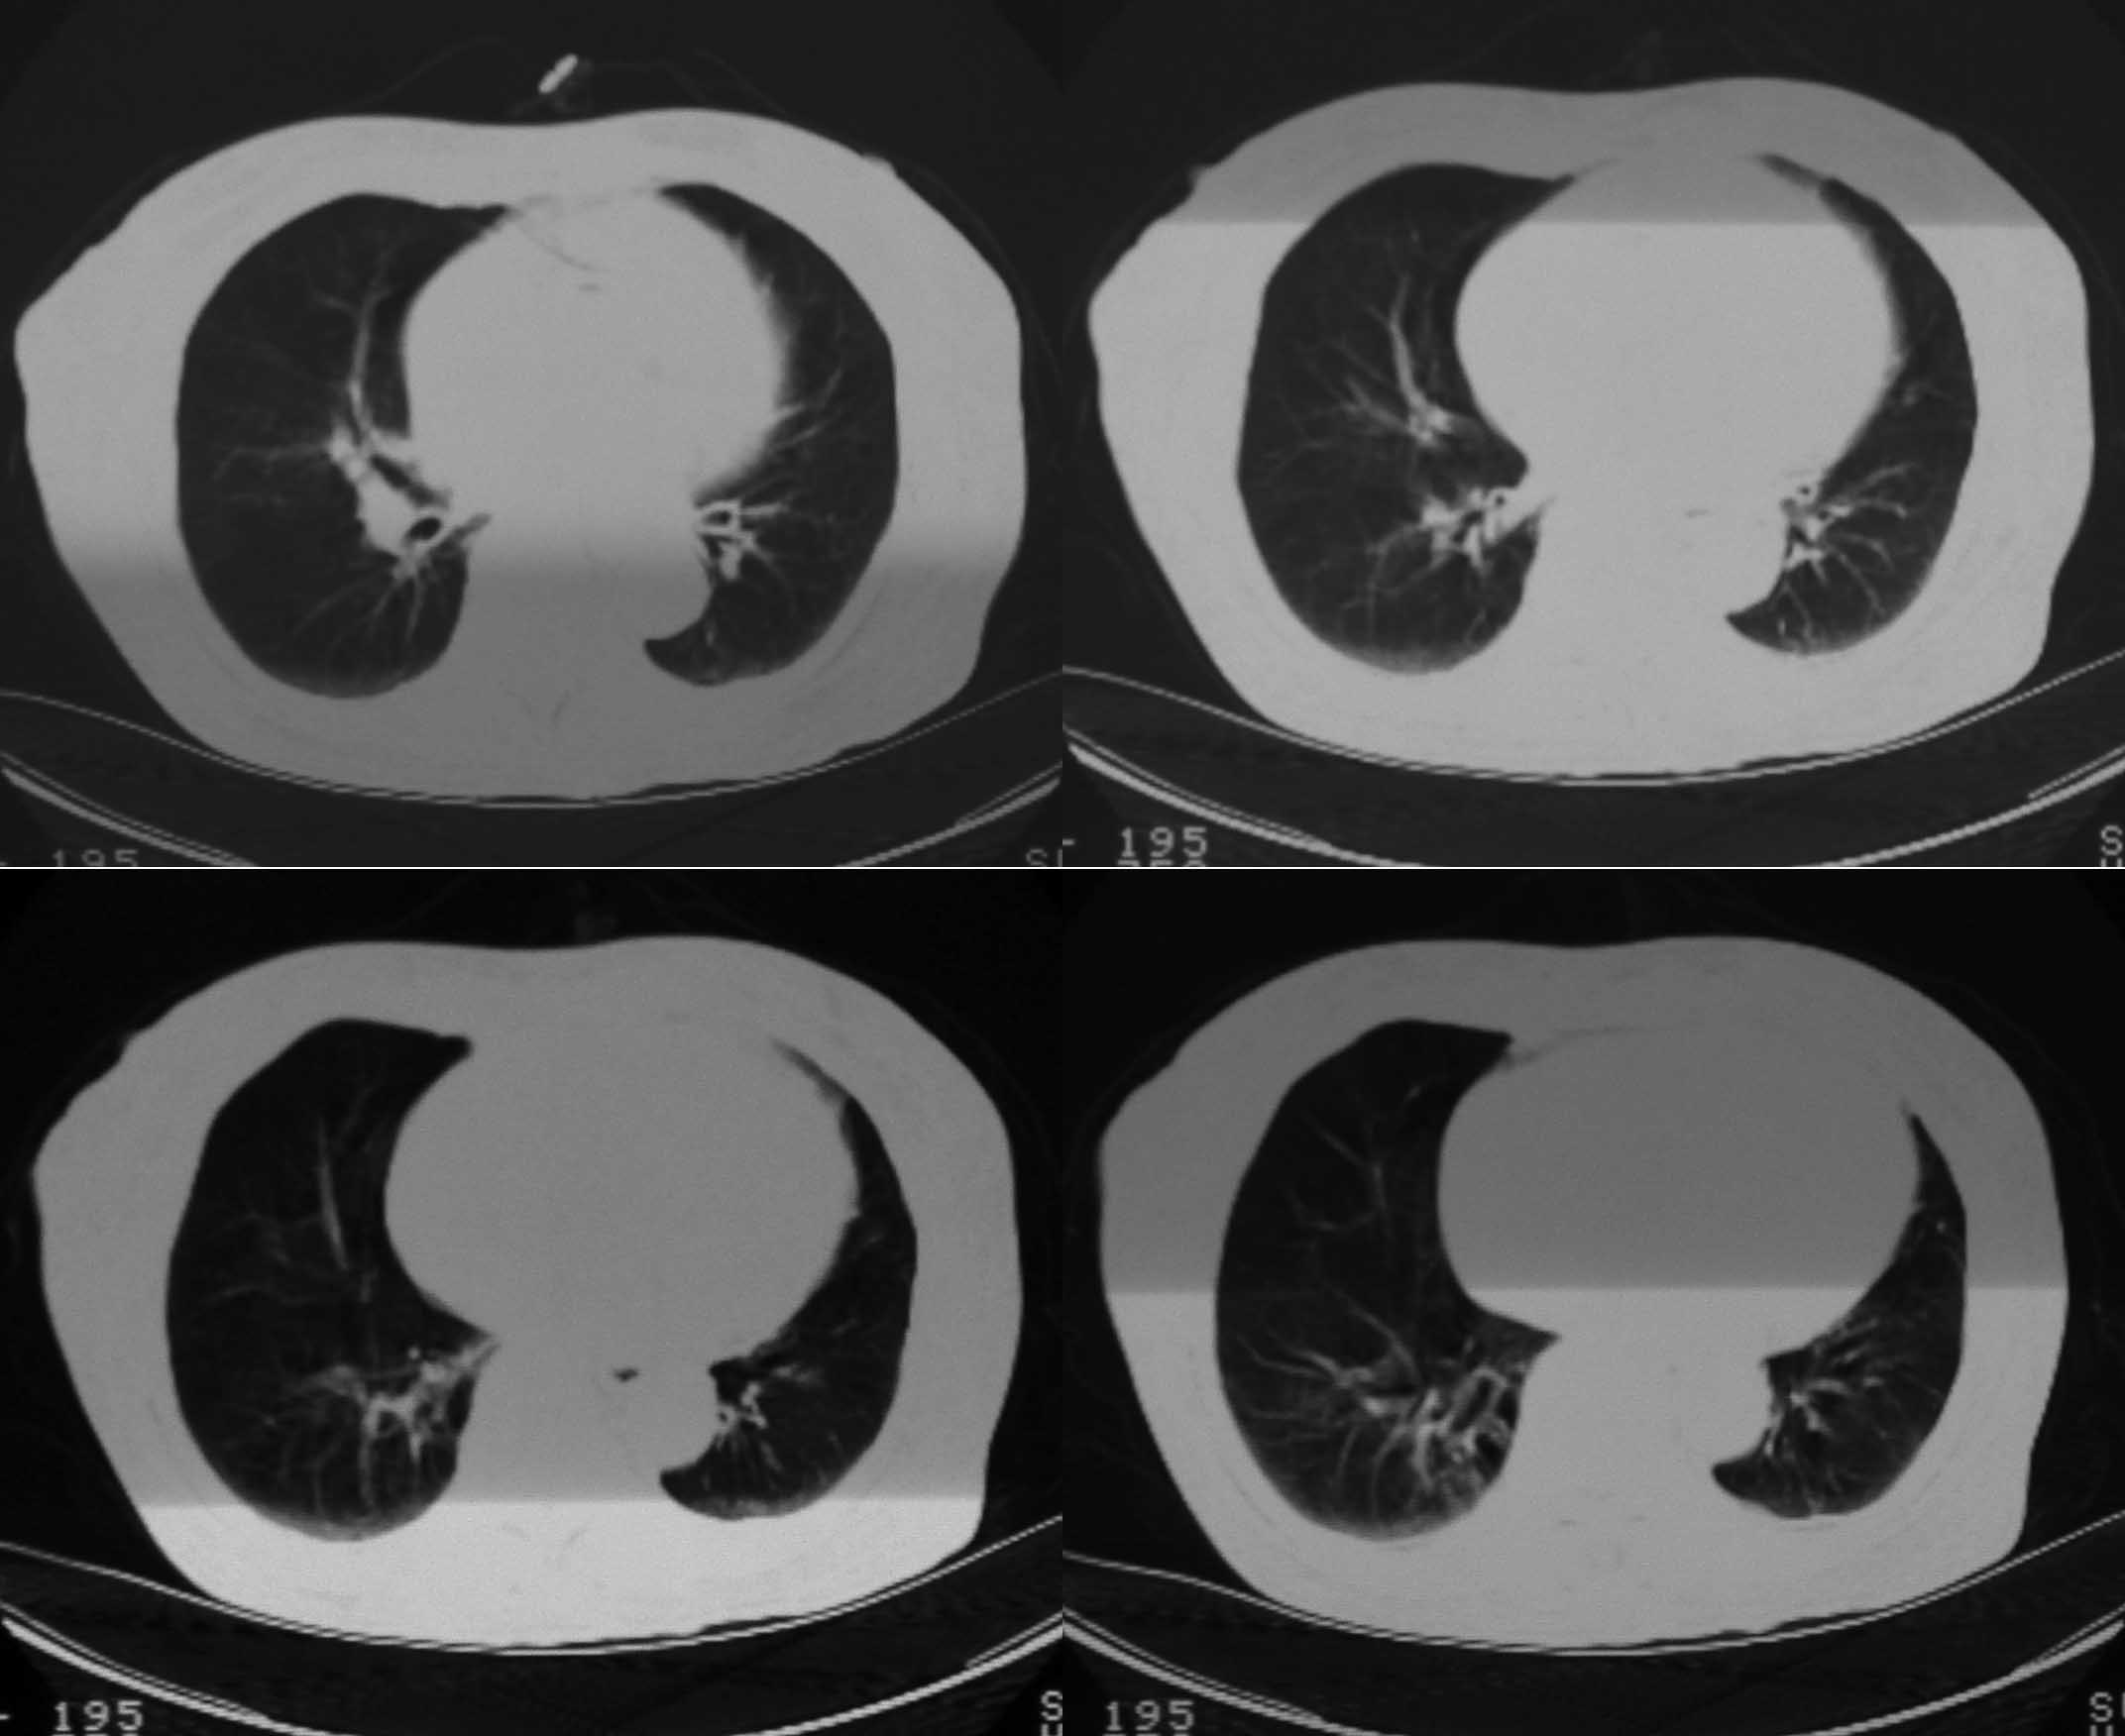

女69岁。时有咳漱、咳白色痰请老师们看看箭头所指是什么?ct值约-36.报告应该怎样写?谢谢!

说实话,图像质量一般,楼主所指为局部胸膜肥厚表现

楼主所指为局限性胸膜肥厚

楼主所指为局限性胸膜肥厚  ct值是因为肺窗

局限性胸膜肥厚  ct值有时也不准

局限性胸膜肥厚,心影增大,建议心超检查